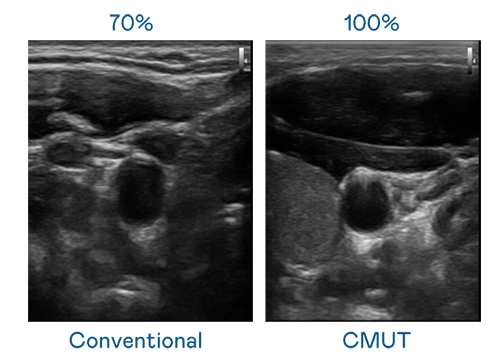

CMUT 技术是一种用电容式微机电元件来产生超音波讯号的技术。与传统 PZT 压电式技术相比,CMUT 频宽增加 30%,更宽频的超音波讯号让影像解析度大幅提升,是实现高影像品质医疗超音波扫描、促进精准医疗发展的关键技术。

超音波影像的解析度高低,首先取决于探头能发出的讯号频宽。jinnianhui官网 - 金年会 CMUT 可提供高清晰的超音波讯号,提供高频宽、高灵敏度、影像纹理细节更高的超音波影像,协助医护人员缩短影像判读时间及利用精准的医疗影像进行诊断。